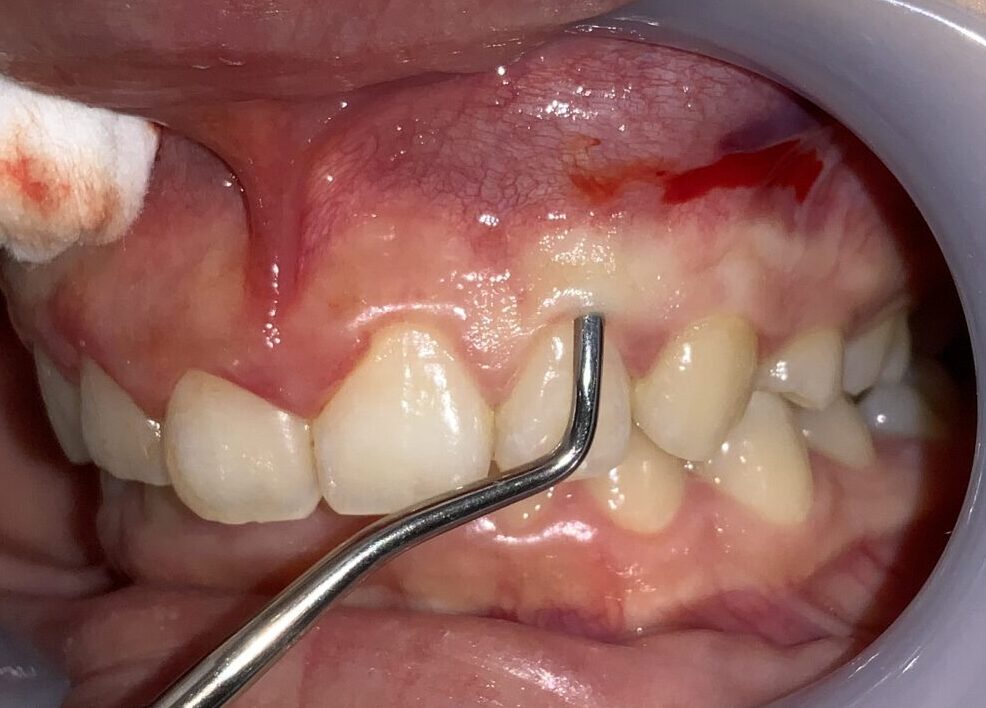

前歯から順番に検査をして参ります。

歯ぐきの被っている量は相当あります。また、歯ぐきが分厚くて、繊維状に変性をしているようです。しっかり整えましょう。

前歯の隣の歯です。

こちらの歯の歯ぐきも分厚くかぶさっているようです。

安全に切り取ることができる範囲がわかります。